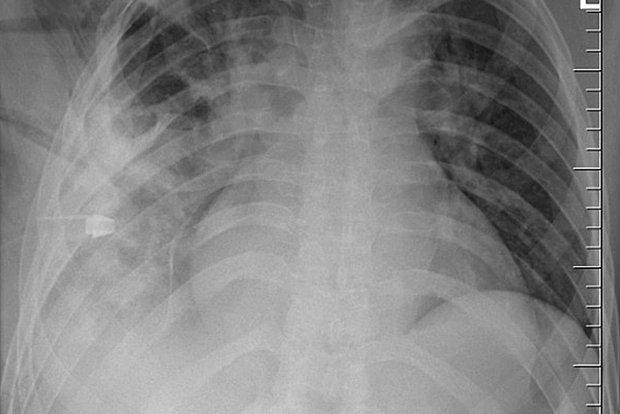

44-летний мужчина обратился в больницу из-за гнойных выделений в районе соска. Врачи удивились, что мужчина не жаловался на боли в груди, проблемы с дыханием и кашель, и сделали ему рентген. Тогда они и обнаружили, что внутри пациента застрял нож. Лезвие вошло рядом с правой лопаткой и не задело ни одного органа, поэтому он спокойно жил с ним.

По словам пациента, около восьми лет назад на него напали с ножом, после чего он попал в больницу с многочисленными ранениями. Тогда врачи не смогли провести рентгенологическое обследование и просто зашили его раны. Впоследствии мужчину ничего не беспокоило, поэтому он и не обращался за помощью. Гной стал сочиться из его тела из-за омертвевших тканей, которые образовались вокруг инородного объекта.

Врачи успешно удалили нож из груди мужчины. Спустя 11 дней ему удалось восстановиться.